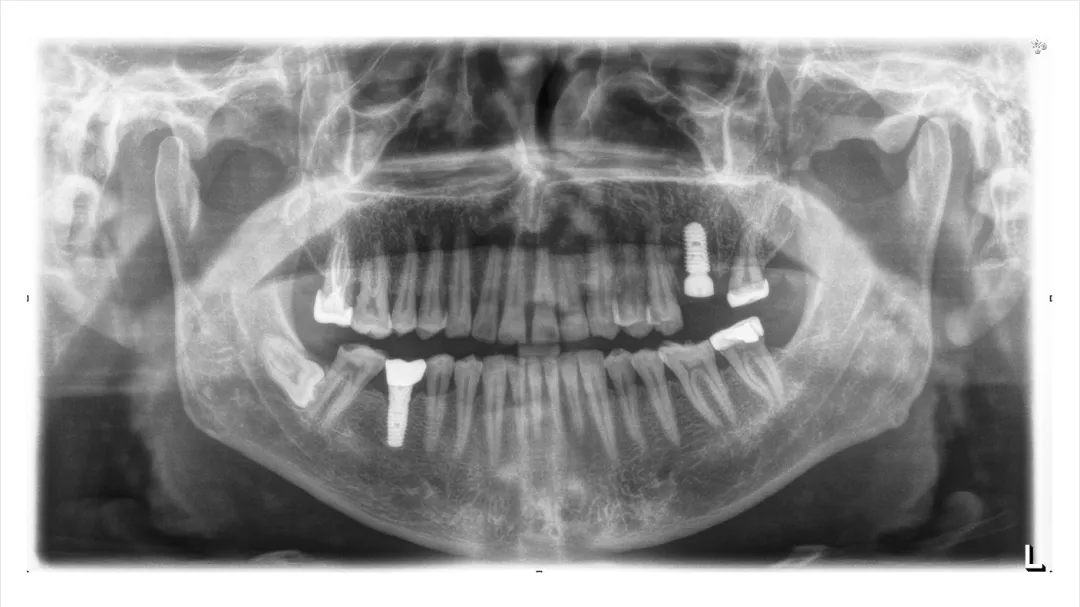

病例分享:患者男,诊断左上六慢性根尖炎劈裂;处置:基础治疗+即刻种植(种植前中后进行光动力疗法照射1min(2次)